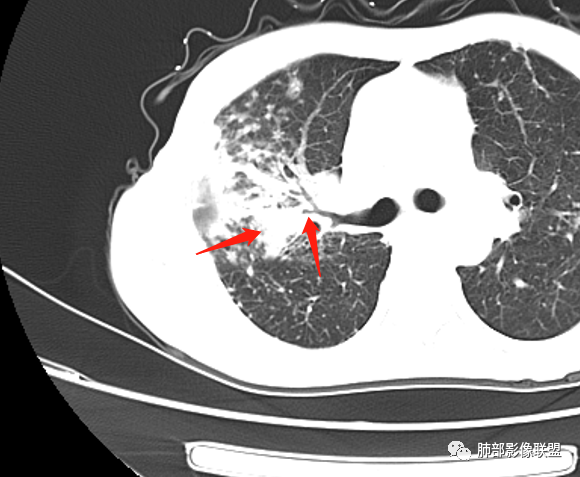

就这里不让人放心,是占位吗?支气管是截断的,没有凹陷或者突出阻断,阻断前稍扩张

患者老年女性,亚急性起病,主要症状表现为咳嗽、咳痰半月余,查体:双现呼吸音粗,双肺可闻及痰鸣音。胸部CT:双上肺胸膜下可见多发小叶实变影,双上肺可见多发小叶中心性结节及小叶间隔增厚,右上肺后段可见亚段性实变影,内见多发空洞,前段可见GGO及树芽征,后段局部支气管闭塞,肺门淋巴结肿大并钙化。病灶整体:有气道、间质播散,一元论考虑肺结核合并支气管结核可能性大,建议好好查痰;这样病灶:明显实变 空洞 气道播散,若是结核,痰涂片找到抗酸杆菌应该没问题。建议支气管镜检查助诊,了解有无支气管结核及合并腺癌的可能。 医学百科网 | YxBaike.Com

1、树芽征

3、小叶间质增厚,有索条影

4、反晕征 医学百科网 | YxBaike.Com